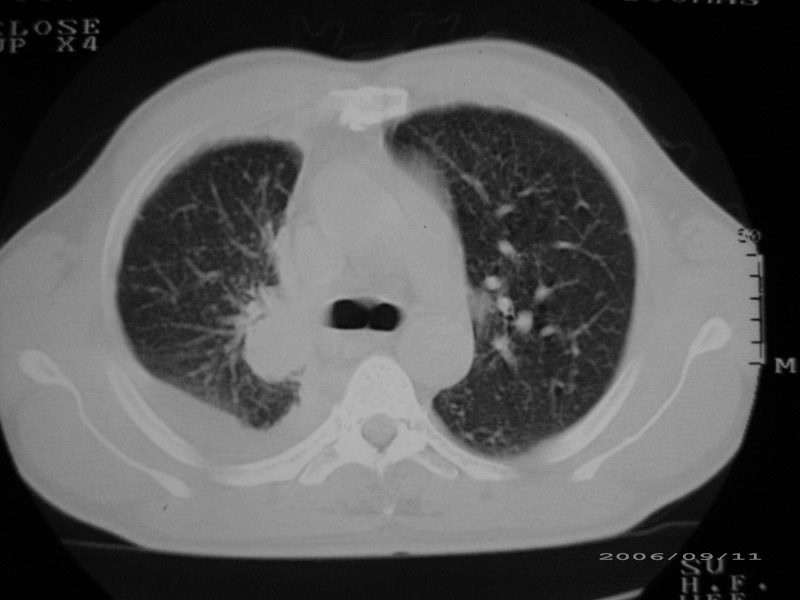

以下是引用守望可可西里在2006-9-11 15:29:00的发言:[br][br] ct平扫表现:右侧胸膜腔缩小,积液,胸膜增厚且不均匀、不规则,以纵隔胸膜增厚为主,边缘呈锯齿状,并见附壁内突之结节状肿块影。右肺含气量减少,纹理聚集,右肺门中下部见数个肿大的淋巴结。纵隔无移位,内未见明显肿大淋巴结,双侧主支气管以及各叶、段支气管比较通畅。。[br] 考虑:右侧胸膜恶性间皮瘤,伴肺门淋巴结转移。